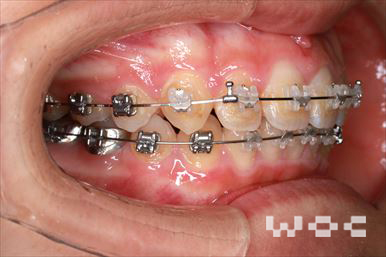

出っ歯上のみ舌側矯正、下はエッジワイズ装置

上は舌側矯正で希望。第一選択は上顎両側第一小臼歯の抜歯だったが、ボーダーラインケースであり改善なければ抜歯することを了承のうえ、非抜歯治療で開始。非抜歯で終了しました。

- 年齢:28歳女性

- 主訴:出っ歯、前歯が曲がっているのが気になる

- 基本矯正料金:103万円

- 治療期間:1年8ヶ月

- 非抜歯